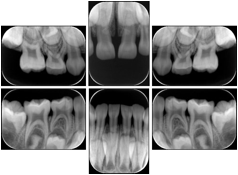

1. A patient in rural Canada visits a general ophthalmologist and is found to have diabetic macular edema. The general ophthalmologist would like to discuss the case with a retina specialist before performing laser surgery. A fluorescein angiogram is done with multiple retinal images taken in a timed series after an intravenous injection. The images along with a Structured Display are shared via a Health Information Exchange with a retina specialist in Calgary, who opens them using his Ophthalmology EMR software and consults via phone with the general ophthalmologist. Both physicians view the images in the same layout so the retina specialist can provide accurate guidance for treating the patient.

2. A patient in rural Iowa visits his primary care physician for management of diabetes. Three non-mydriatic (patient's eyes are not dilated) photographs are taken of the back of each eye, and forwarded electronically along with a Structured Display to an ophthalmologist in Iowa City. The ophthalmologist reads the photos in an agreed upon layout so there is no mistake about what portion of which eye is being viewed. The ophthalmologist is able to tell the primary care physician that his patient does not need to come to Iowa City for face to face ophthalmologic care, but that there is a particular view of the left eye that should be photographed again in 6 months.

Ophthalmic Retinal Study Structured Display

Figure OO-3. Ophthalmic Retinal Study Structured Display